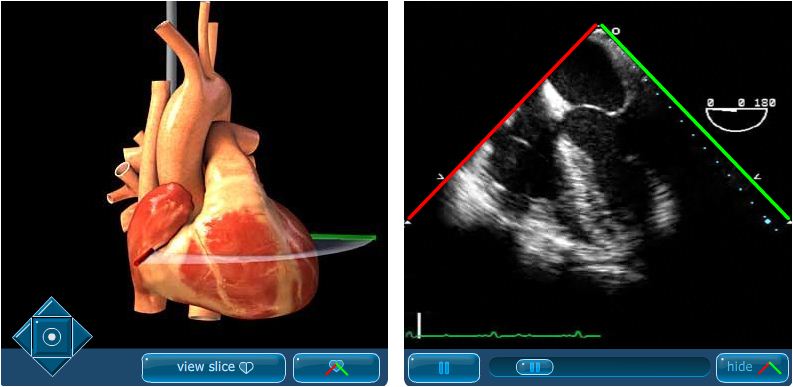

Aspectos generales (superficiales) de un procedimiento ecocardiográfico (transesofágico) para información al público general. ECOCARDIOGRAFIA PRÁCTICA CON MODELOS HEARTWORKS & VIMEDIX Realidad Virtual Fantastico curso de eco transesofagica, altamente recomendable, he aprendido muchisimo, Muy buen equipo!!. Volumen 1, No 4, octubrediciembre 03 MG Ecocardiografía principios y aplicaciones 227 edigraphiccom parte se absorben (atenuaciones) y otras se reflejan (ecos).

Agora que você já sabe o que é ecocardiografia transtorácica, se você acha que tem problemas cardíacos e precisa do exame, procure seu médico e converse sobre seus sintomas, especialmente aqueles que causam dor, desconforto ou interferem nas atividades diárias. Permite Ecocardiografia Transtorácica (ETT), Ecocardiografia Transesofágica (ETE) e ultrassonografia abdominal / pélvica em uma única plataforma Simulação de imagens de ultrassom e funções cardíacas, pulmonares e abdominais Reproduz em tempo real os atributos visuais, físicos e ergonômicos do ultrassom em Realidade Aumentada 3D. A ecocardiografia transesofágica é um exame de cardiologia Marque os seus exames de diagnóstico na rede Hospital da Luz Este website usa cookies essenciais, analíticos, sociais e de personalização para oferecerlhe uma boa experiência de navegação e acesso a todas as funcionalidades.

Vimedix Ecocardiografia Transtoracica Transesofagica Simulacao Medica